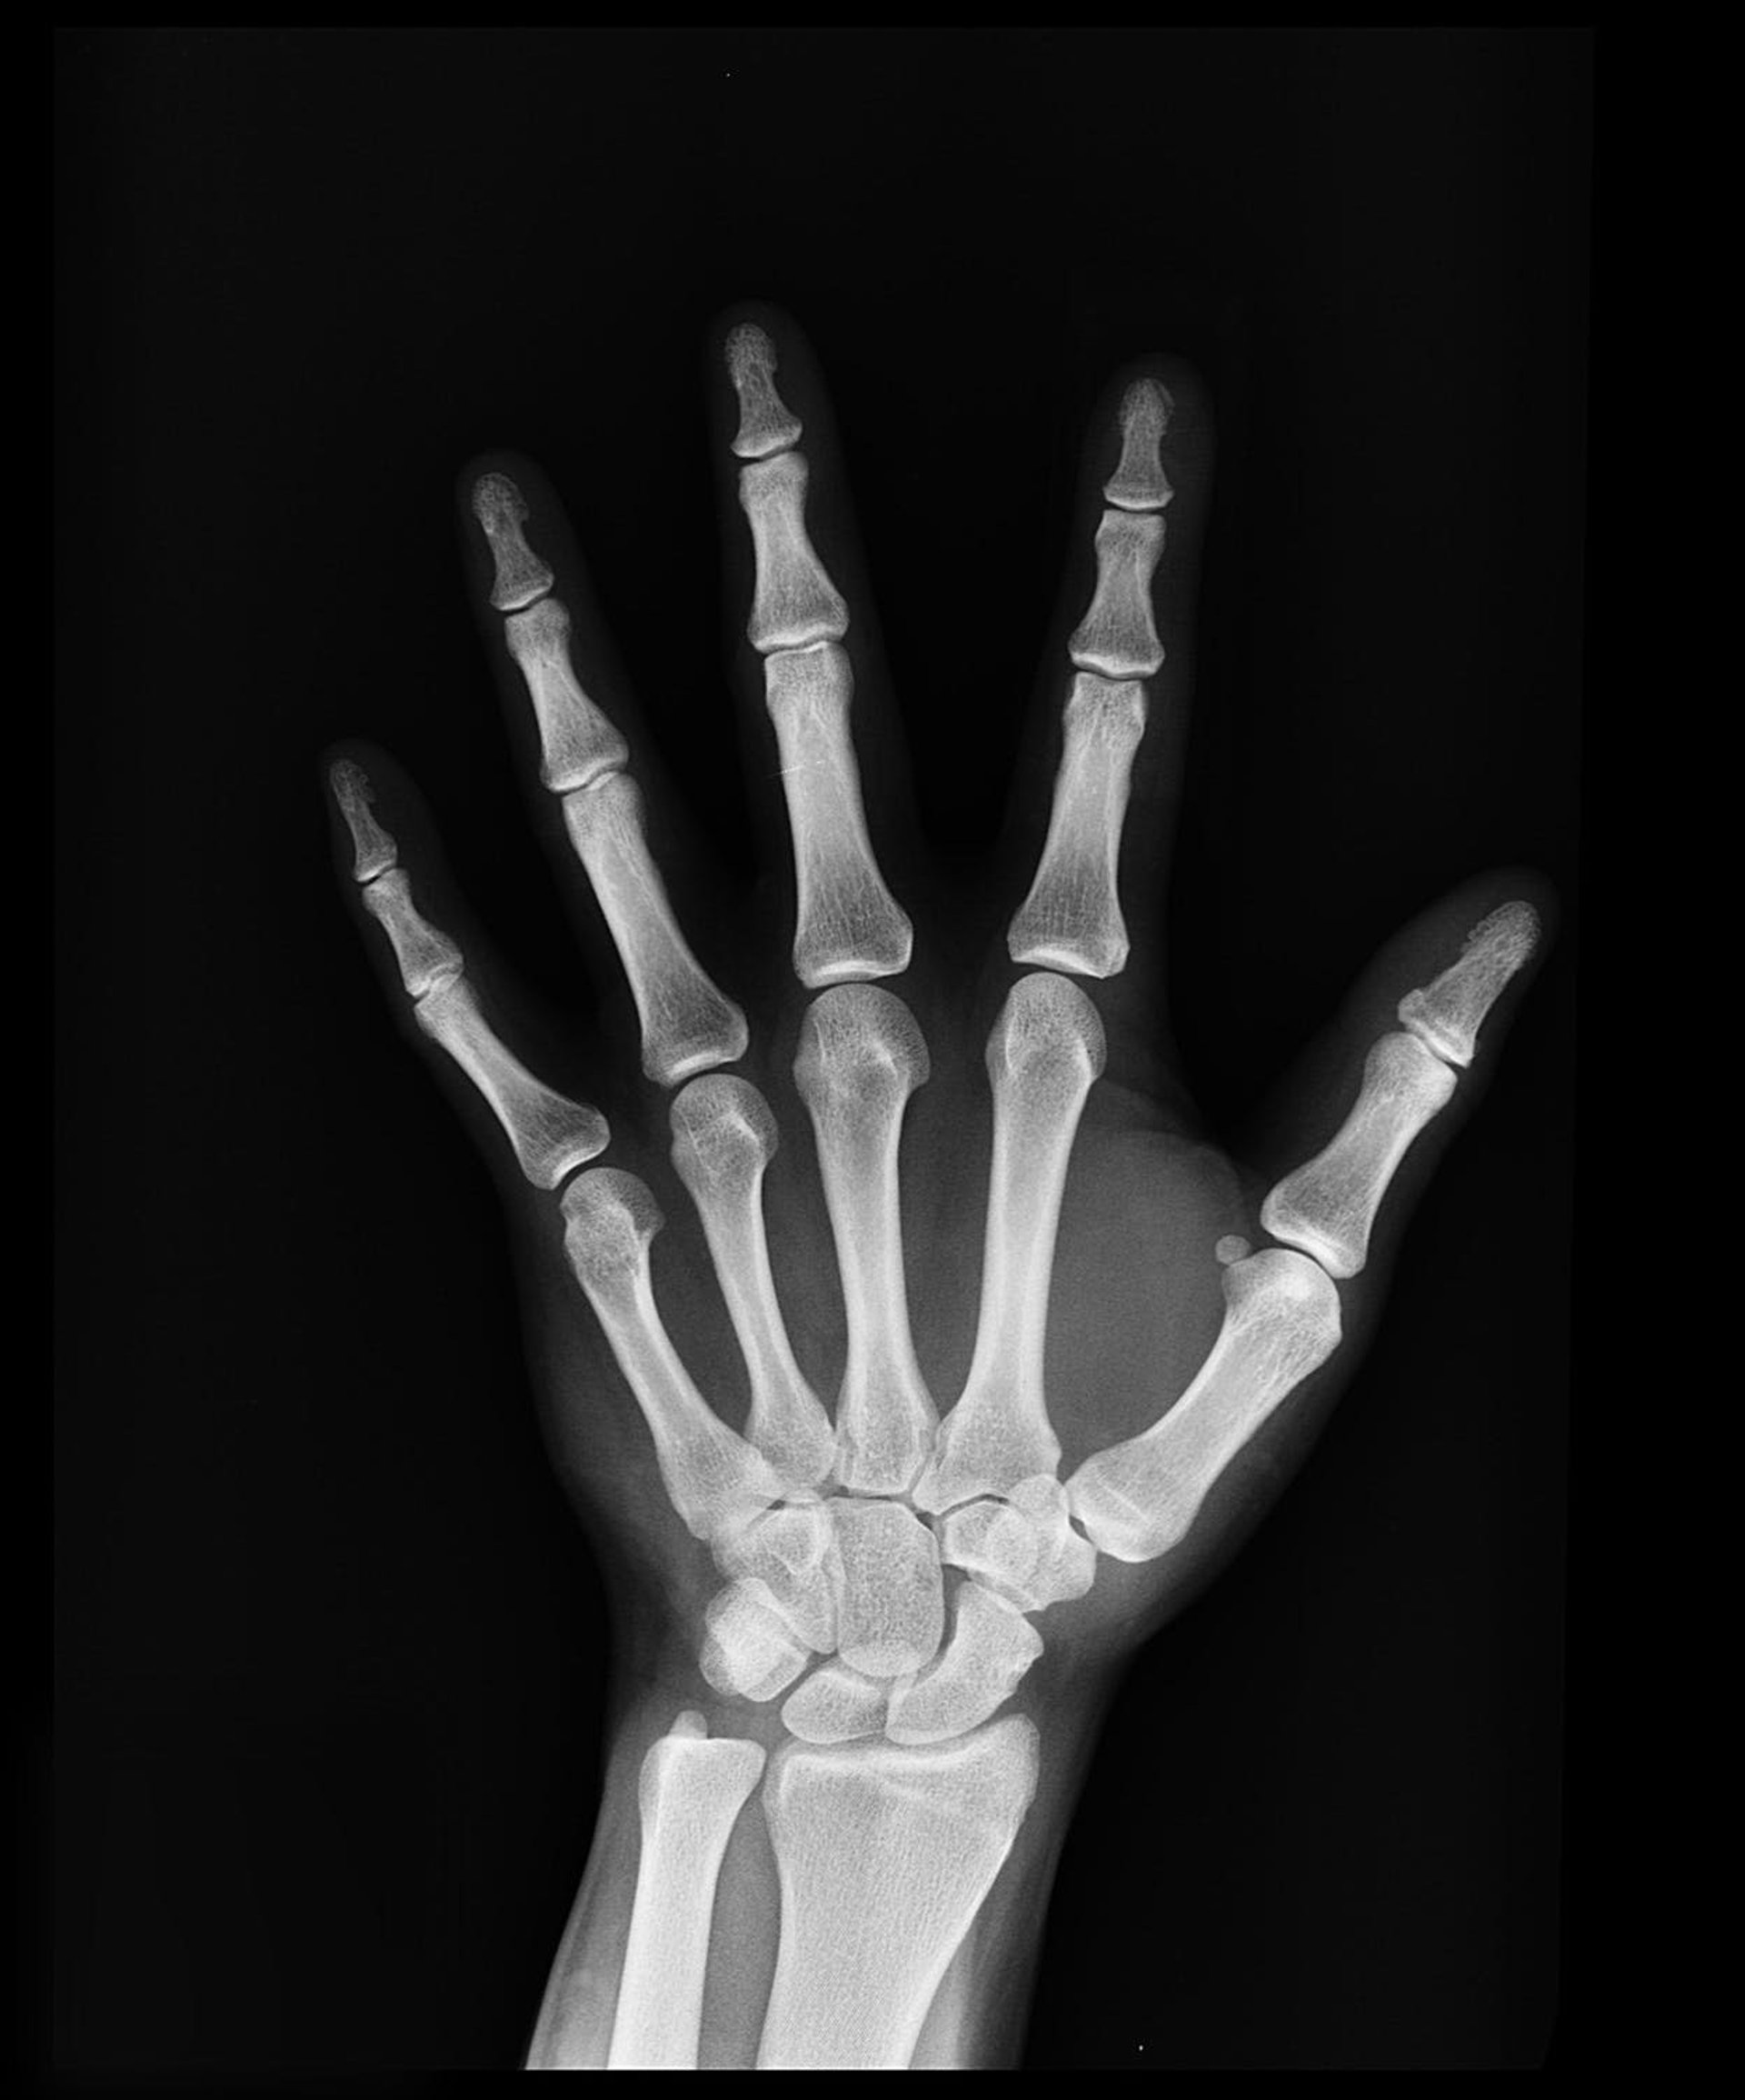

Archivo - Radiografía de mano

Archivo - Radiografía de mano - UGR - Archivo